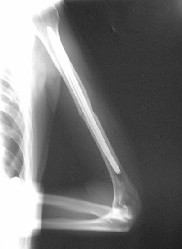

Al examen físico de ingreso se aprecia paciente en condiciones estables, con dolor a la palpación de arcos costales de hemitórax izquierdo y deformidad en brazo izquierdo. En la radiografía se aprecia fractura de tres arcos costales izquierdos y fractura oblicua corta de tercio medio de húmero izquierdo.

Se ingresa paciente y se decide tratamiento quirúrgico enclavado endomedular con clavo expandible tipo Fixion®.

Se coloca paciente en decúbito supino, con brazo sobre el tórax y se realiza abordaje posterior de tercio distal de húmero. Se realiza osteotomía en paleta humeral y se introduce clavo expandible con ayuda de intensificador de imagenes.

Se

verifica radiológicamente la reducción y se introduce solución a presión para la

expansión del clavo. Se comprueba estabilidad y se cierra por planos.

Aquí vemos el resultado radiológico final.